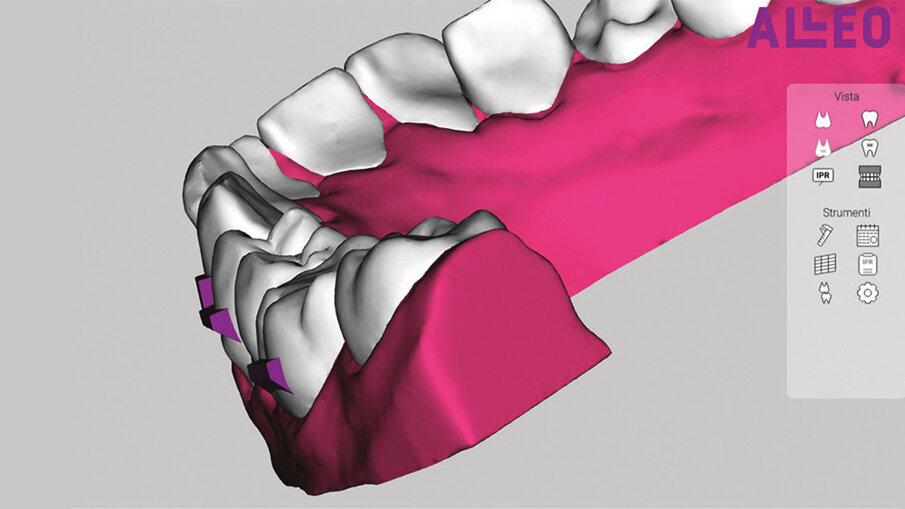

Con View ALLEO (Figg. 5a-5c) avremo la possibilità di analizzare i valori dentali nella tabella dei movimenti; in base ai valori di intrusione e l’ipercorrezione che abbiamo programmato, utilizzeremo una serie di ausiliari che garantiranno il successo e la risoluzione del caso (bite-ramp anteriori, elastici di Classe II, attachments rettangolari orizzontali bisellati gengivalmente o occlusalmente a seconda della direzione della forza). L’utilizzo dei bite-ramp (Fig. 6) anteriori è fondamentale per svincolare le arcate, permettendo l’estrusione posteriore e impedendo l’effetto (in questo caso indesiderato) bite-block degli allineatori. L’intrusione degli incisivi inferiori programmata produrrà sull’allineatore una forza di reazione che tenderà a scalzare posteriormente l’allineatore stesso, tuttavia ciò non avverrà proprio per la presenza di attachments posteriori bisellati occlusamente, che produrranno un’estrusione dei settori posteriori necessaria ad aiutarci nell’apertura del morso (Figg. 7a-7e).

Figg. 5a-5c_View ALLEO ci permette la visualizzazione del set-up, la quantità di stripping necessaria per ottenere un corretto allineamento, la posizione degli attachments, oltre al report biomeccanico preciso di tutti i movimenti dentali proposti all’interno del set-up.

Figg. 5a-5c_View ALLEO ci permette la visualizzazione del set-up, la quantità di stripping necessaria per ottenere un corretto allineamento, la posizione degli attachments, oltre al report biomeccanico preciso di tutti i movimenti dentali proposti all’interno del set-up.

Figg. 5a-5c_View ALLEO ci permette la visualizzazione del set-up, la quantità di stripping necessaria per ottenere un corretto allineamento, la posizione degli attachments, oltre al report biomeccanico preciso di tutti i movimenti dentali proposti all’interno del set-up.

Per la risoluzione del caso sono stati pianificati 30 allineatori superiori e 20 inferiori più una rifinitura successiva, di altri 10 allineatori per arcata, per una durata complessiva di circa 15 mesi di trattamento. Al termine della terapia (Figg. 8a-8h) le arcate si presentano ampie, allineate e ben coordinate; le linee mediane risultano coincidenti, le relazioni occlusali di destra sono state migliorate ottenendo una piena Classe I, mentre a sinistra si raggiunge una buona classe I molare-premolare, lasciando solo il 23 in classe II per non aprire spazi tra l’incisivo laterale. Nonostante l’affollamento fosse moderato, il caso preso in esame mostrava alcune criticità, parliamo della presenza di alcuni elementi dentari in arcata superiore, in particolare del 22 che presentava una rotazione di 29° (vedi Figg. 5a-5c). A tal proposito, la letteratura ci ha ampiamente dimostrato come la derotazione di alcuni elementi dentali in arcata superiore (vedi incisivi laterali) e inferiore (vedi canini e primi premolari), sia uno dei movimenti più difficoltosi da ottenere con la tecnica degli allineatori7.